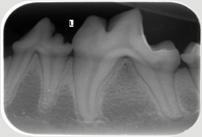

Neben der allgemeinen Untersuchung und der Untersuchung der Zahntaschen mittels Parodontalsonde sind ZAHNRÖNTGEN unumgänglich für eine komplette Diagnostik von Parodontalerkrankungen und bei Zahnresorptionen vor allem bei der Katze (FORL). Dabei werden spezielle Techniken mit Dentalfilmen wie beim Menschen verwendet.

In der Kleintier-Ordination Mittertreffling wird eine moderne digitale Entwicklung verwendet, die die Strahlenbelastung für Ihr Tier verringert. Ohne Zahnröntgen wird das Ausmaß des Knochenverlustes oft unterschätzt und bei der Katze viele Zahnresorptionen übersehen oder unterschätzt. Zudem ist bei einer wie in der Tier-Zahnheilkunde in einer Sitzung durchgeführten Wurzelbehandlung (Endodontie) eine Kontrolle durch Zahnröntgen unbedingt notwendig. Selbst Tumoren können sehr gut erkannt werden und auch die Kontrolle einer Zahnbewegung (Orthodontie) sollte durch Zahnröntgen erfolgen.

Zahnröntgen Oberkiefer Hund P4 Zahnröntgen Unterkiefer Hund normal Zahnröntgen Oberkiefer Hund dreiwurzliger P3